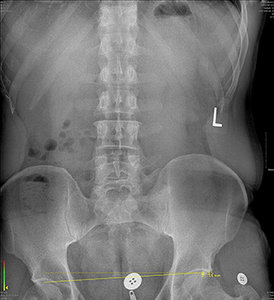

FIG 2 Standing X-ray with bilateral custom orthotic support.

Sadly, the majority of these patients, after being adjusted, are back in to the same adaptational situation that is leading to low back pain before even making it back to their car.

Some common symptoms associated with lower extremity structural imbalances are: foot, knee, hip and low back pain. Finding relief from these symptoms can be achieved with musculoskeletal treatment and activity modification; but frequently, these symptoms are persistent due to excessive, uneven tissue loading, resulting in repetitive-stress injury.

There was an unremarkable orthopedic exam. Digital laser scan of the plantar vault revealed symmetrical lateral arch collapse. In addition, an apparent 14 mm reduction deficit was noted in the right femur upon X-ray.

The patient was fitted with custom three-arch foot orthotics and lumbopelvic X-rays were repeated. With the orthotics, the actual reduction deficit in the right femur was measured at 6 mm. A 6 mm heel lift was added on the right and follow-up X-ray revealed a zero-deficit femoral head height measurement.